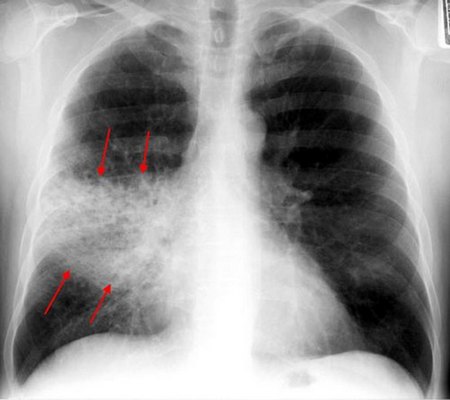

Рентгенологические изменения в легких при крупозной пневмонии, разнообразны и зависят от стадии процесса. Вначале отмечается усиление легочного рисунка, затем появляются очаги затемнения, которые сливаются между собой. Образовавшаяся тень соответствует доле или сегменту легкого. Восстановление нормальной прозрачности легких происходит постепенно и длится до 2-3 недель. Динамика рентгенологических изменений при пневмонии, зависит от сроков начала лечения.

Рентгенологическое исследование: выявляют плотный гомогенный инфильтрат, соответствующий доле или нескольким

Стоит отметить, что многие люди путают крупозную пневмонию с очаговой. Но на самом деле эти патологии различны между собой. В случае прогрессирования очаговой пневмонии на рентгене будет видно, что поражены определённые дольки лёгкого. Если же прогрессирует крупозная пневмония, то на рентгене будет чётко видно поражение целой доли лёгкого, которая и состоит из небольших долек. Все это говорит о том, что площадь поражения при крупозном типе значительно больше, чем при очаговом. Поэтому такая патология и протекает тяжелее.

Наиболее информативным методом диагностики является рентген. Он даёт возможность выявить наличие и распространённость патологического процесса. Рентген проводят как взрослым, так и детям при подозрении на развитие этой патологии.

Основные признаки крупозной пневмонии, которые можно выявить при помощи рентгена:

• поражённая доля имеет выпуклые границы;

• однородное затемнение доли;

• реакция плевральной оболочки очень чёткая.

Если при помощи рентгена врачу не удалось точно поставить диагноз, то прибегают к КТ или МРТ.